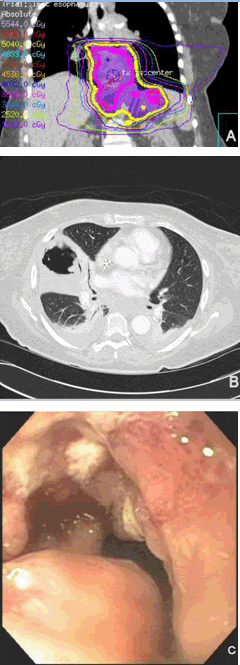

A 69-year-old African-American female also presented with a three-month history of moderate to severe dysphagia. She was obese but did have laboratory evidence of malnutrition. Upper endoscopy with biopsies revealed moderately differentiated invasive adenocarcinoma of the distal esophagus, esophagus at 34 to 38 cm from the upper incisors, extending less than 1 cm past GEJ. By endoscopic ultrasound, stage IIIA (uT3, uN0, M0) was assigned. There was no complete obstruction of the lumen. Computed tomography and positron emission tomography did not reveal any evidence of distant metastases. She was advised to undergo esophagectomy following a course of neoadjuvant concurrent chemoradiation after consultations with the physicians on the multidisciplinary care team. Furthermore, esophageal stent was recommended and a fully covered SEMS, 18x120 mm in size, was placed across GEJ. The patient then started radiotherapy for a total planned dose of 50.4 Gy/28 fractions, given simultaneously with weekly paclitaxel and carboplatin chemotherapy. During preoperative chemoradiotherapy, she complained of persistent chest pain and symptoms of reflux while lying flat. After the daily treatment fraction 19, the patient presented to the hospital with dyspnea at rest. Opacity in the right lung was identified on X-ray, which after two weeks of hospital stay worsened and was ultimately diagnosed as necrotizing pneumonia of the right middle lobe of the lung. There was also radiographic evidence of aspiration in both lower lungs. The patient received intravenous antibiotics and supplemental oxygen. Chemoradiotherapy was aborted after fraction #25, and the patient expired on hospice shortly thereafter. The most likely cause of death was determined to be aspiration pneumonia due to incompetence of the stented lower esophageal sphincter (Figure 2).

Figure 2: Endoscopic and radiographic images in Case 2. (A) Diagram of body region receiving radiotherapy, (B) Single axial slice of contrast enhanced computed tomography of the thorax, taken just prior patient's expiration, demonstrating necrotizing pneumonia with a large cavitary lesion in the right middle lobe with an air-fluid level, as well as scattered infiltrative changes throughout both lungs, likely representing combination of pneumonia/aspiration, (C) View of the distal esophageal tumor just prior to stent insertion.